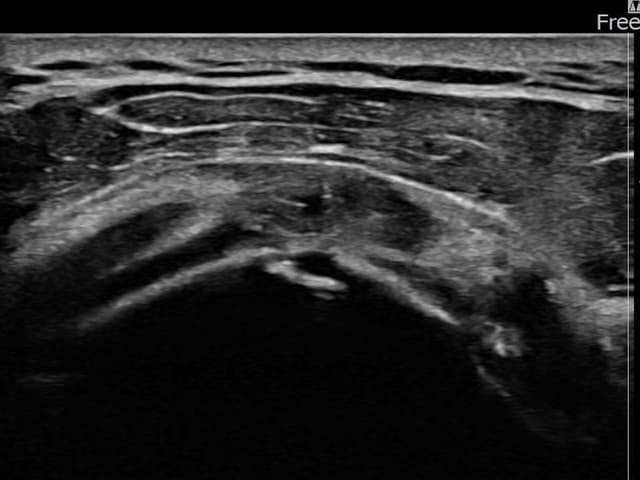

[촬영시기:22.09.05~22.12.08]

[어깨인대 축소봉합술] 우측 어깨 통증과 야간 통증으로 수면 장애가 있어 내원하셨습니다.